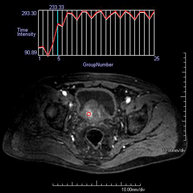

Prova diagnòstica no invasiva que consisteix en l'obtenció d'imatges d'alta definició anatòmica de la glàndula prostàtica mitjançant l'ús d'un camp electromagnètic i ones de ràdio (amb un emissor i un receptor). No utilitza radiació ionitzant. S'utilitza una bobina endorectal per obtenir imatges de màxima definició anatòmica de la pròstata i permetre fer l'estudi espectroscòpic (estudi a nivell molecular que ajuda a diferenciar les cèl·lules d'origen maligne o tumoral). També es realitza l'estudi amb contrast paramagnètic, que aporta una millor definició tissular. Aquesta prova dura uns 40 minuts, durant els quals el pacient haurà d'estar el més quiet possible. Requereix una neteja del còlon com a preparació prèvia. Aquesta prova està especialment indicada en aquells pacients amb sospita de neoplàsia de pròstata, amb neoplàsia de pròstata coneguda per l'estadiatge tumoral, per a l'estudi de localització del tumor prostàtic com a guia o mapa per a la biòpsia, per al seguiment dels pacients amb neoplàsia de pròstata tractats amb tractament quirúrgic o radioteràpic, davant d'una sospita de reincidència de la neoplàsia de pròstata, etc. - RM de Cos sencer (Total body)